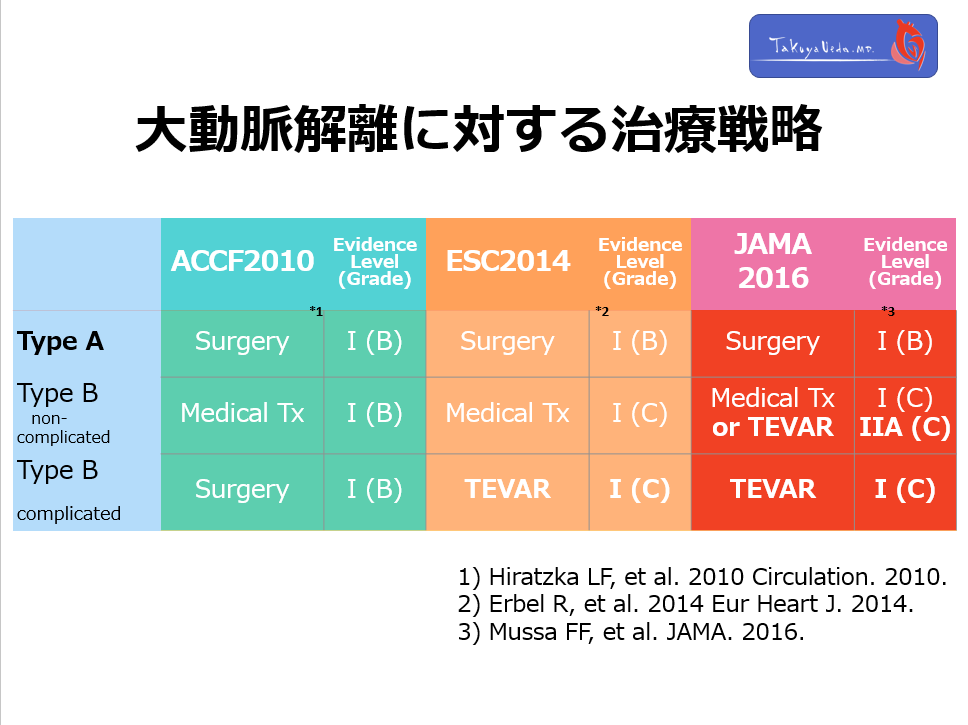

You need to update you knowledge about the Tx strategy of AoD

◆ Following dramatical improvement of surgical management for acute AoD, and good result of TEVAR for acute type B AoD, strategy to treat AoD and IMH has been dramatically modified.

◆ TEVAR treatment is actively indicated for complicated Type B AoD and IMH.